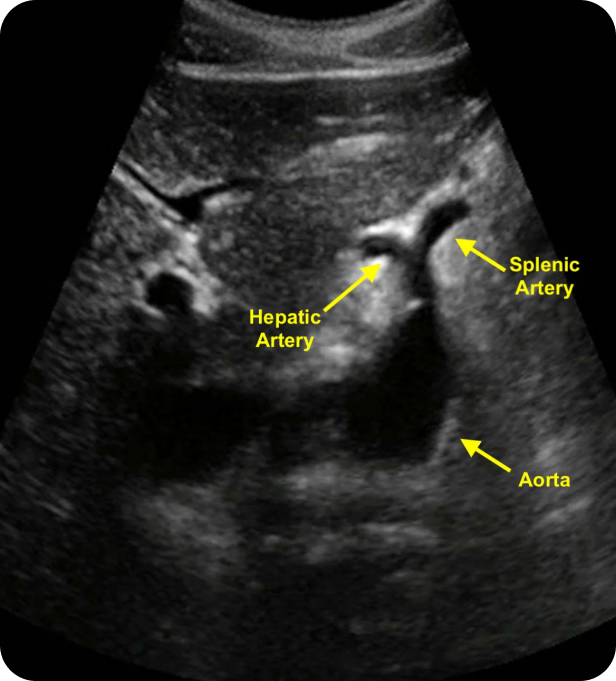

How This Ultrasound Helps in Detecting Specific Types of Problems/Diseases

A vascular ultrasound is a non-invasive diagnostic tool used to:

Identify Blockages: Detect narrowing or occlusions in the arteries caused by plaque buildup to prevent stroke or limb loss.

Assess Blood Flow: Evaluate the velocity and direction of blood flow to identify venous reflux or arterial stenosis.

Screen for Aneurysms: Provide critical AAA (Abdominal Aortic Aneurysm) screenings to detect life-threatening arterial bulges.

Evaluate Dialysis Access: Perform detailed imaging for dialysis access evaluation to ensure the viability of grafts and fistulas.

Monitor DVT: Rapidly scan for blood clots in the deep veins to prevent pulmonary embolisms.